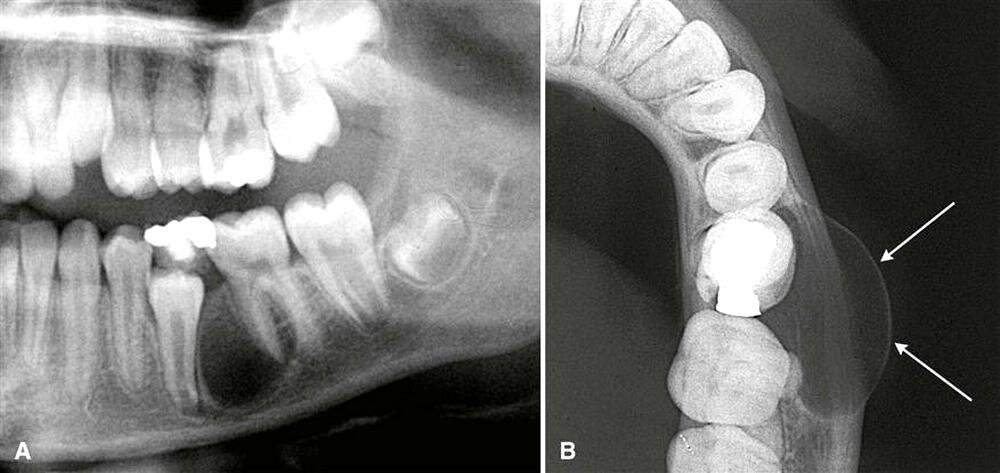

Цементома — это крупная костная масса, которая образуется в твёрдом зубном дентине. Она характеризуется высокой минерализацией и наличием множества волокон, сходных с структурой цементной пульпы. На рентгенограмме она обычно представляет собой круглую или овальную область с особыми признаками минерализации и резорбции.

Периапикальная цементома, имеющая форму округлого или овального выступа, обычно обнаруживается в области периапикальных изменений на рентгенограмме. Цементома может вызывать боль в соответствующей области и стать причиной осложнений.